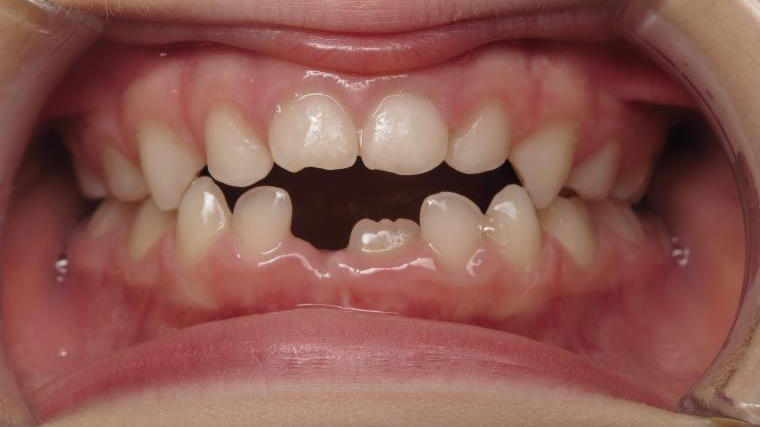

14 béance inversé gauche 5 ans

inversion postérieur coté droit et espace entre l'arcade du haut et du bas (béance)

bilan début et en cours de traitement